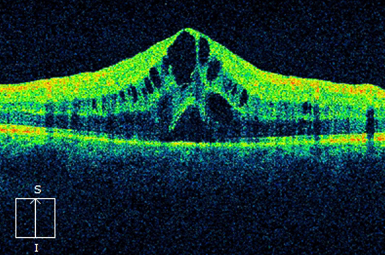

Macular Edema (CME)

Many eye conditions lead to macular swelling. Treatments include intravitreal injections, laser photocoagulation, periocular injections, and occasionally vitrectomy surgery.

Image courtesy of Heidelberg Engineering, Inc.